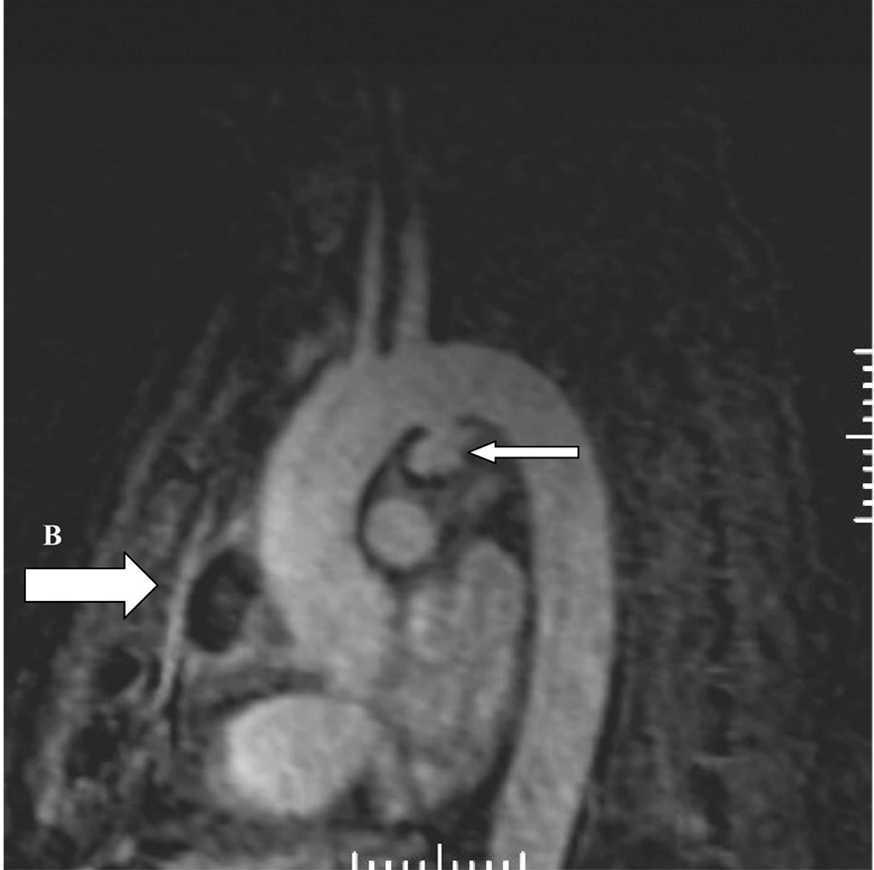

Consultado el caso con el Servicio de Cirugía Cardíaca se decide mantener tratamiento médico y actitud expectante. En ecocardiogramas posteriores mantiene mínimo derrame pericárdico, sin signos de taponamiento y con imágenes de organización en su interior. Presenta buena evolución hemodinámica, respiratoria y general, siendo dado de alta de la UCI a los 5 días de su ingreso. En ecocardiograma transtorácico realizado 10 días después, con el enfermo asintomático, se detecta imagen de probable seudoaneurisma en cayado aórtico, y persistencia de derrame pericárdico. Se practica resonancia magnética nuclear torácica que documenta la presencia de un aneurisma en cayado aórtico, distal a la salida de troncos supraaórticos, probable aneurisma de arteria coronaria derecha y colección intrapericárdica (figs. 3, 4 y 5).

Figura 4. Angiorresonancia magnética nuclear torácica: aneurisma en cayado aórtico (A) y colección intrapericárdica (B).